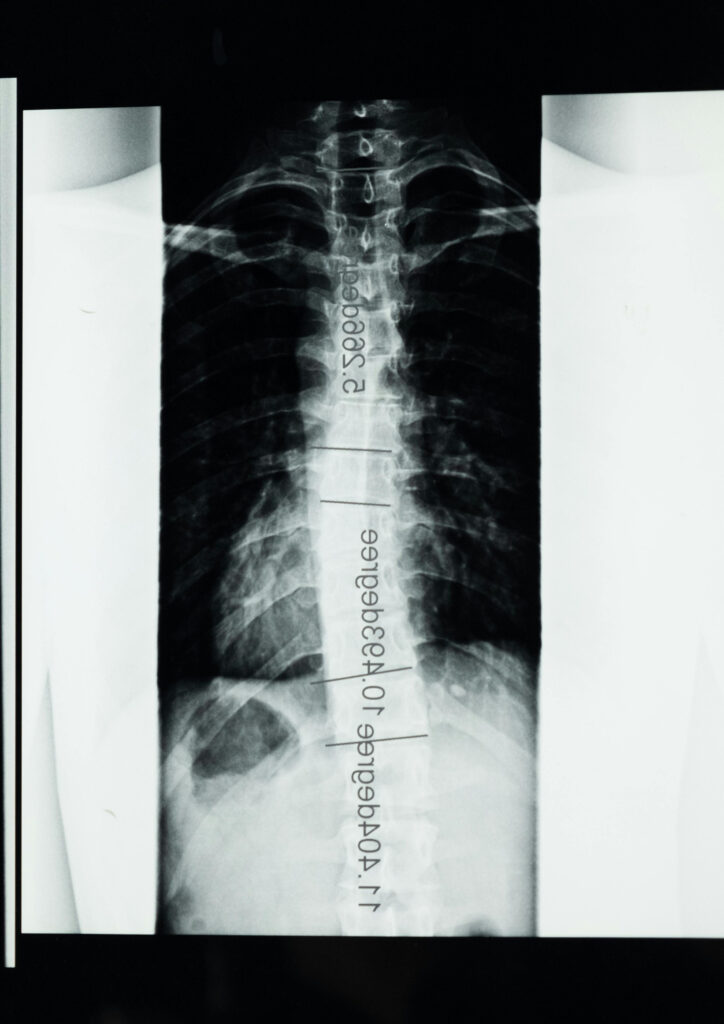

Spinal fusion surgery is a procedure that permanently joins two or more vertebrae (the individual small bones that stack together to form your backbone) to eliminate movement between them. By stabilising the affected segment of the spine, the surgery aims to reduce pain caused by abnormal motion and prevent further damage to surrounding spinal structures.

During the procedure, the neurosurgeon places bone graft material between the affected vertebrae. This graft may come from your own bone, a donor source, or a synthetic substitute. Over time, the bone graft heals and fuses the vertebrae into a single solid unit, providing long-term stability to the spine.